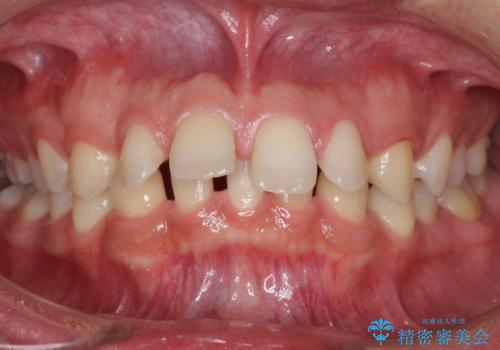

[MTMを行い歯の神経を保存] 歯周補綴ブリッジ